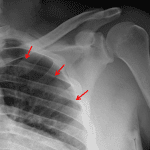

Indication: Trauma

Findings

- No acute fracture or malalignment

- Small left pneumothorax

Diagnosis

- Pneumothorax

Small left pneumothorax.

No acute fracture or malalignment.

Joint spaces are maintained.